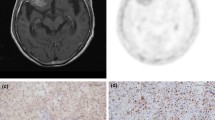

2.4 Ki-67 Immunohistochemistry

Formalin-fixed, paraffin-embedded sections of resected specimens from brain tumor were made for immunohistochemical staining. The Ki-67 index was estimated as the percentage of Ki-67-positive cell nuclei per 500–1,000 cells in the region of the tumor with the greatest density of staining.

In newly diagnosed gliomas, linear regression analysis indicated a weak correlation between T/N ratio and the Ki-67 index (r = 0.45, p < 0.05; Fig. 24.1a). In recurrent gliomas, there was no significant difference between T/N ratio and the Ki-67 index (r = 0.31, p = 0.36; Fig. 24.1b).

Linear regression analysis demonstrates a weak correlation between 4DST T/N ratio and proliferative activity (Ki-67 index) in newly diagnosed gliomas (r = 0.45, p < 0.05) (A). There was no significant correlation between 4DST T/N ratio and proliferative activity (Ki-67 index) in recurrent gliomas (r = 0.31, p = 0.36) (B)